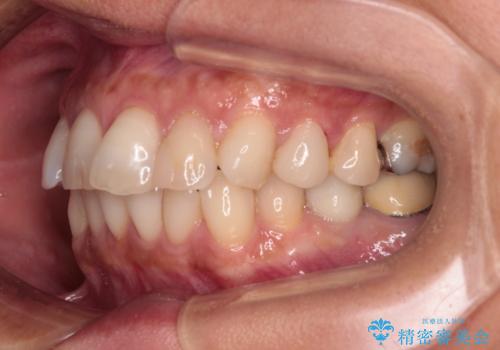

しっかりと装着時間を守ってくださり、来院のタイミングに合わせてインビザラインの装着期間を調整するなど、協力いただいたおかけで、1年半の期間で全てを終えることができました。